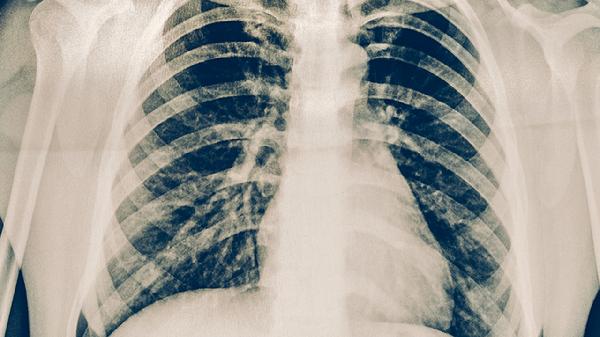

肺癌肺积水可通过胸腔穿刺引流、药物治疗、胸腔闭式引流、化学治疗、靶向治疗等方式治疗。肺癌肺积水可能与肿瘤压迫、淋巴回流受阻、胸膜转移、低蛋白血症、感染等因素有关,通常表现为呼吸困难、胸痛、咳嗽、乏力、体重下降等症状。